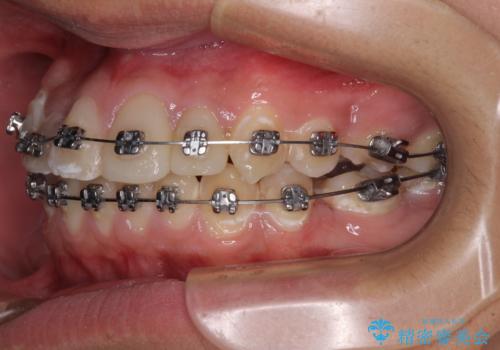

- 矯正装置

- メタルブラケット

矯正治療は、むし歯が酷く抜歯が望ましい歯を1本抜歯して、ワイヤー装置にて整えることとしました。

むし歯が多かったため、ワイヤー矯正中に処置したむし歯が悪化することが懸念されましたが、歯磨きをしっかりと行ってくれたため、とても良好な状態を維持することができました。